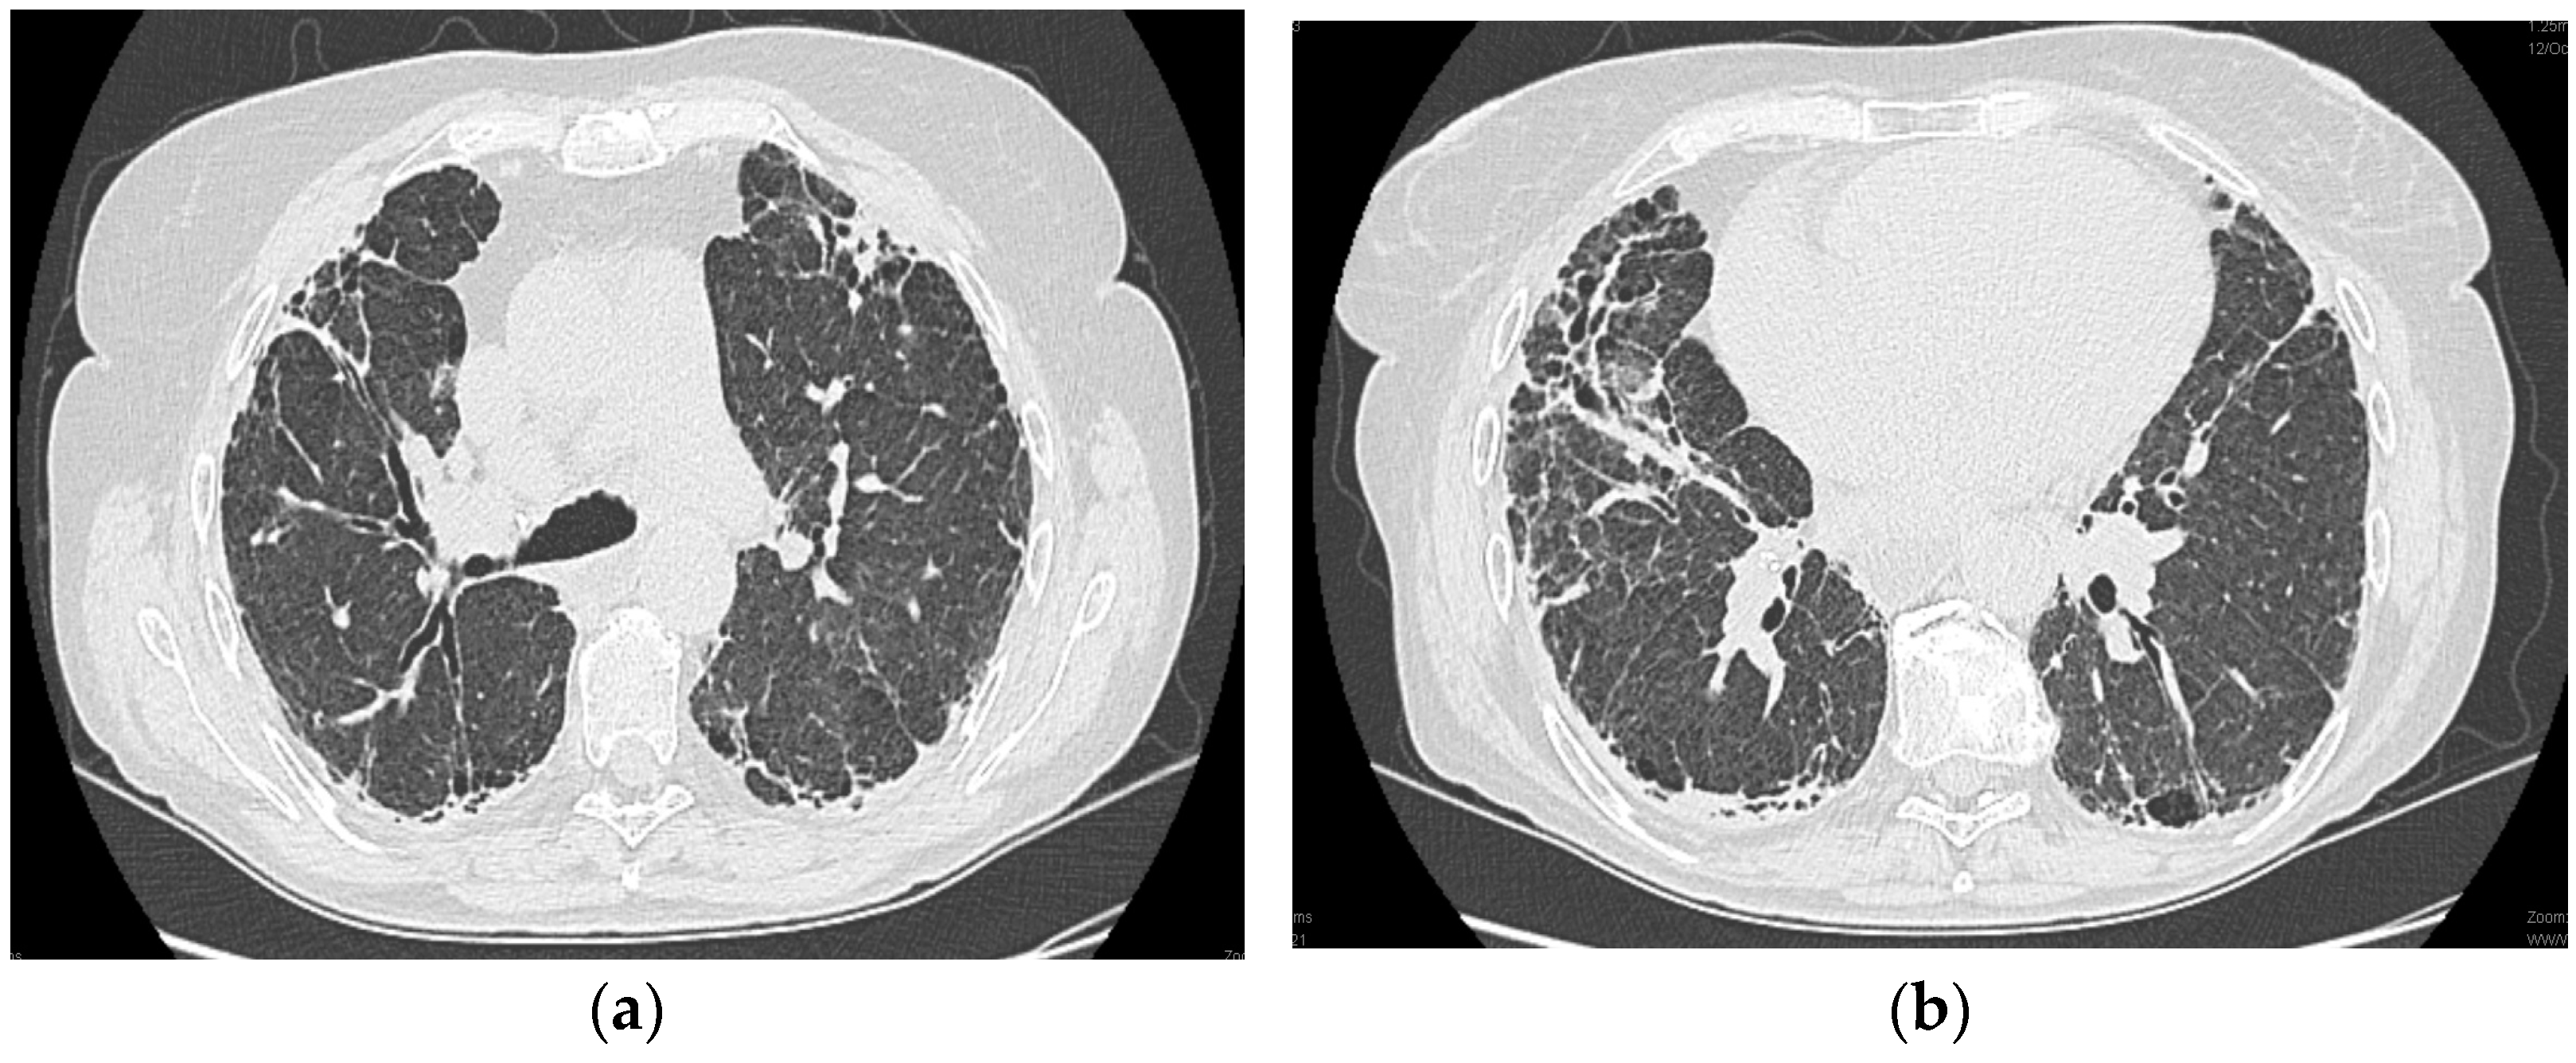

2.1.6. High-Resolution Computed Tomography (12 October 2022) (Figure 2)

Thyroid gland of normal appearance. Advanced fibrotic changes in both lung fields with septal thickening, architectural disorganization, and traction bronchiectasis, with the changes being more important at the basal level of the bilateral lower lobes. Small diffuse calcified granulomas bilaterally, without areas of pulmonary condensation. Absence of suspicious pulmonary nodules. Trachea and bronchi with free lumens. Absence of mediastinal masses. Absence of pleural fluid accumulations. Mediastinal adenopathies up to 17 mm perivascular, 16 mm pretracheal at the right, 18 mm left hilar, 15 mm right hilar, and multiple subcentimeter, some with punctate calcifications. Esophagus minimally dilated with liquid content. Cardiomegaly, pericardial blade up to 18 mm in the right ventricle. Accentuation of dorsal kyphosis. Early degenerative changes in the dorsal spine, without suspicious lesions on the scanned bone segment. Conclusions: Pulmonary fibrosis changes with medium-advanced damage. Pericardial minimum. Esophageal stasis, more likely in the context of achalasia. Bilateral mediastinal and hilar adenopathies, some with calcifications.

Figure 2.

(a,b): Computed tomography of the thorax.